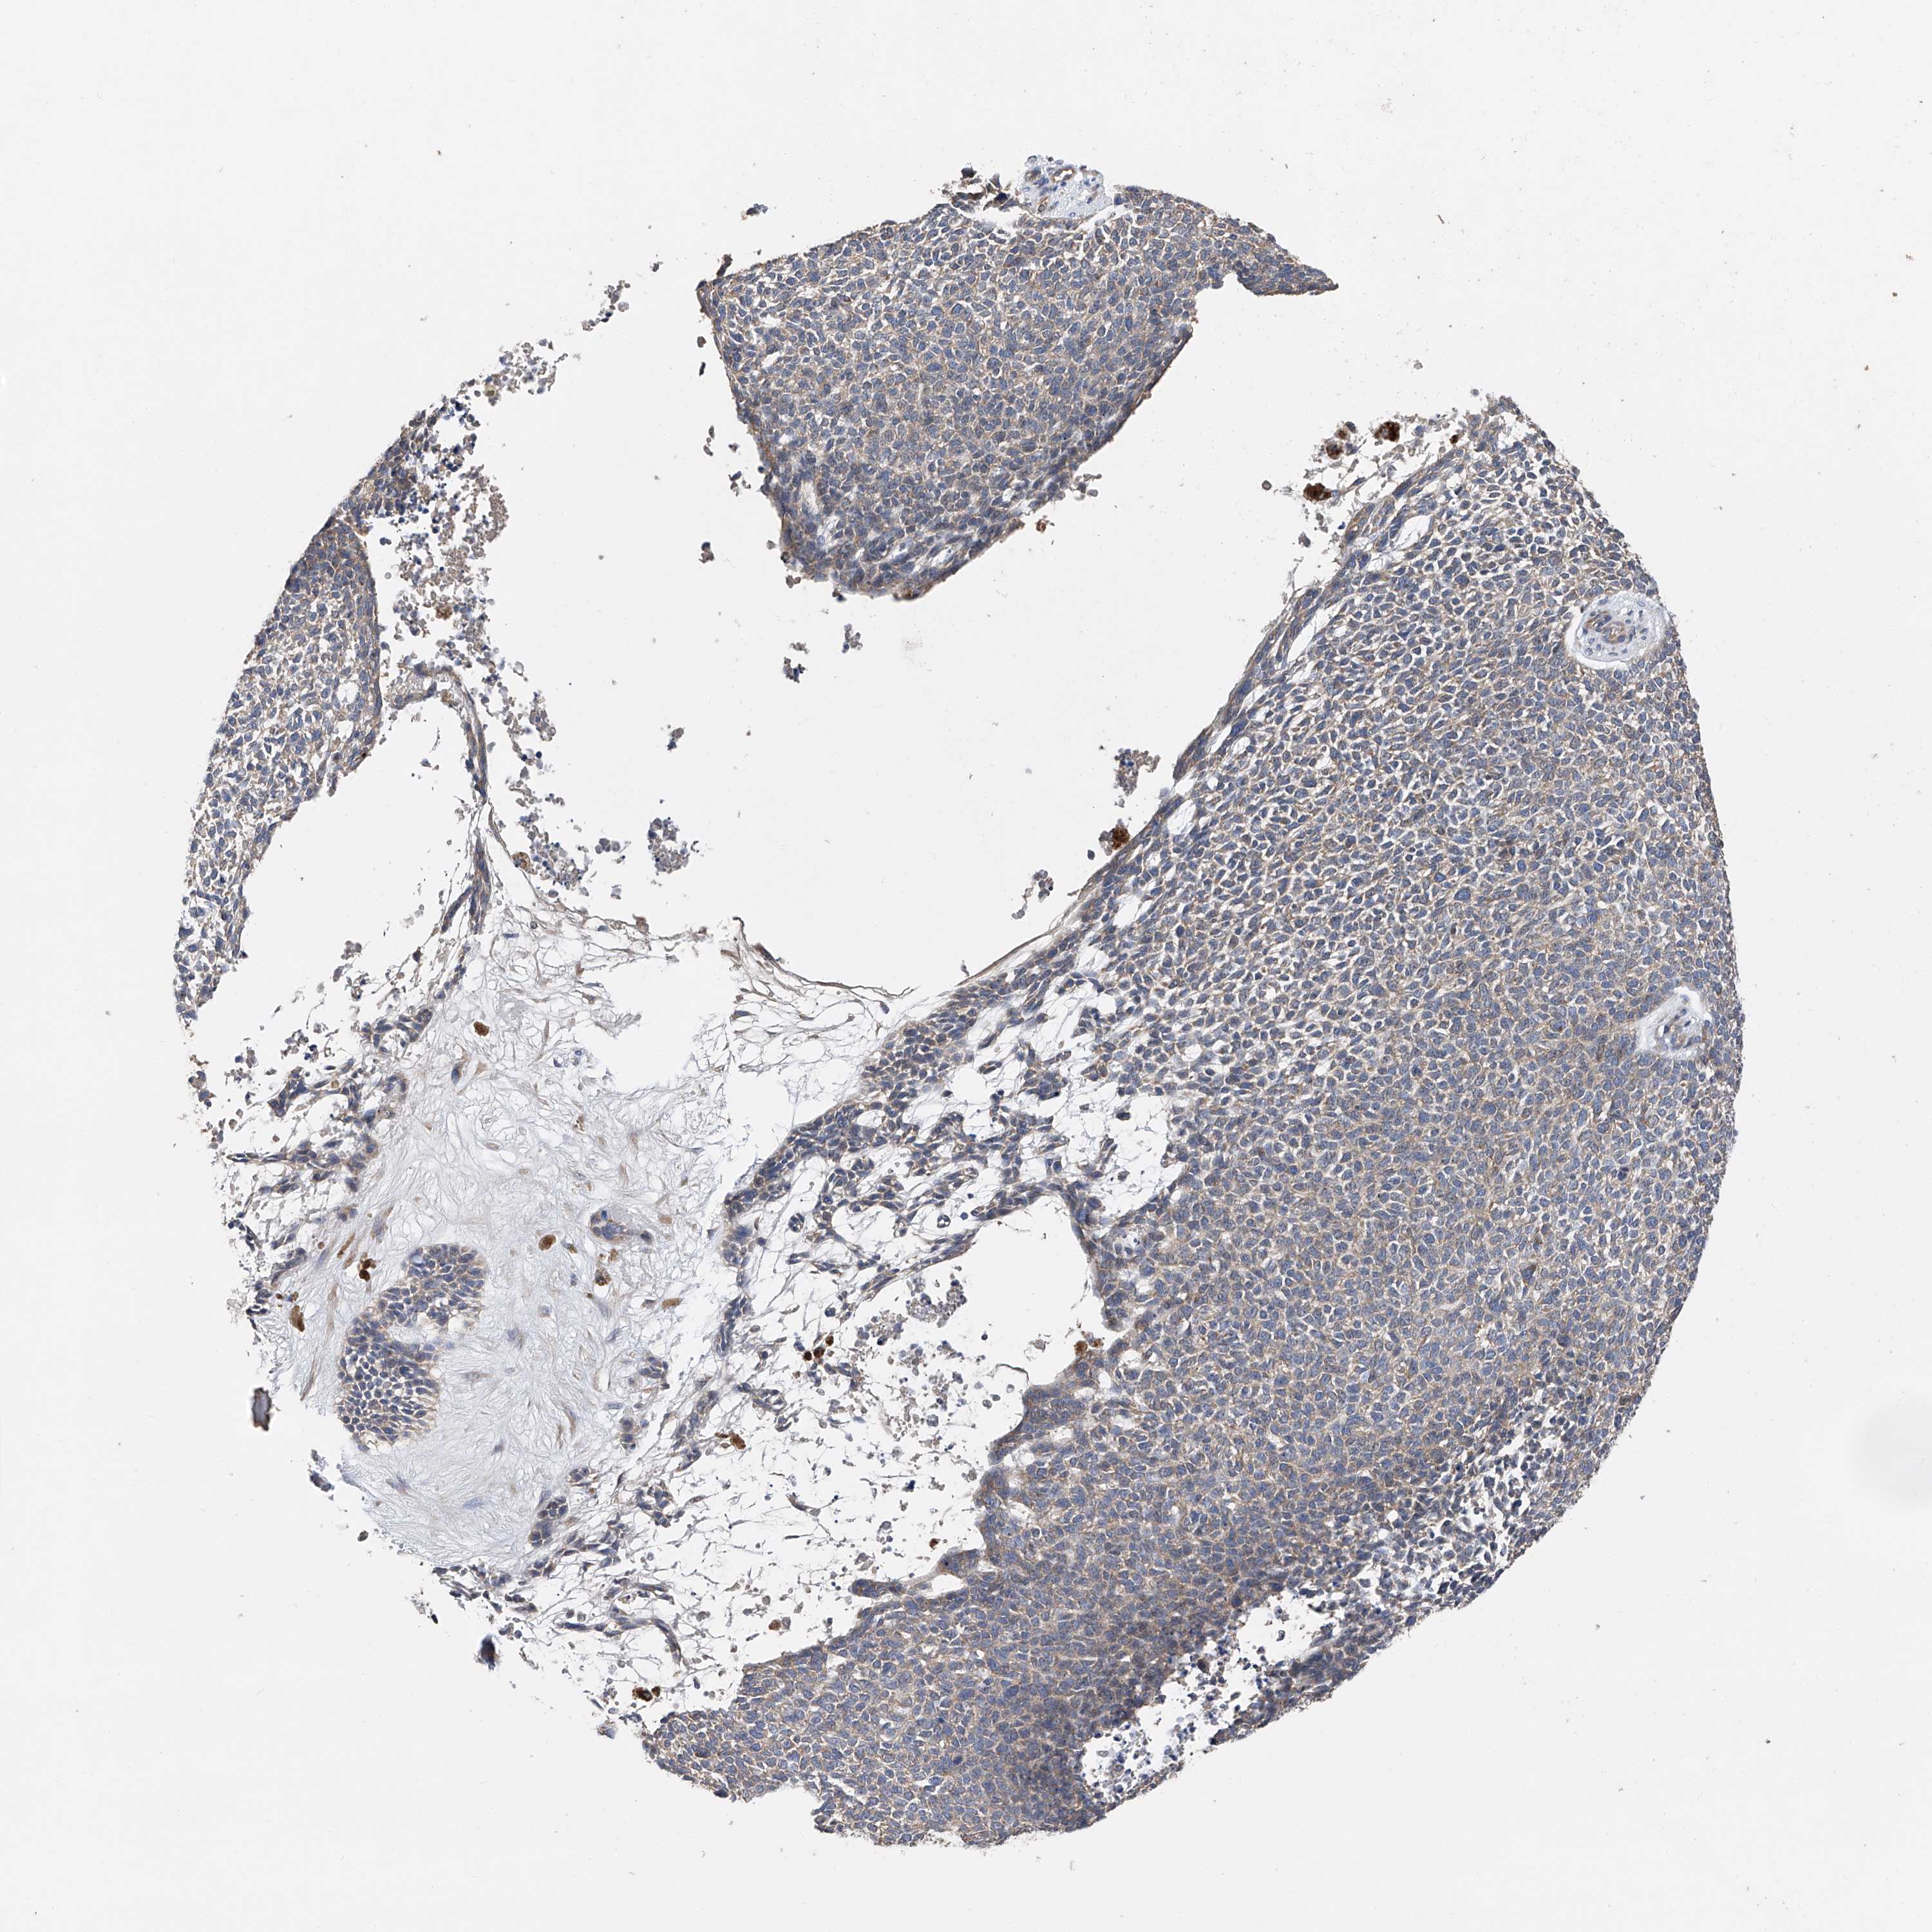

SKIN CANCER - Protein expressioni

A mouse-over function shows sample information and annotation data. Click on an image to view it in a full screen mode. Samples can be filtered based on level of antibody staining by selecting one or several of the following categories: high, medium, low and not detected. The assay and annotation is described here.

Antibody stainingi

Antibody staining in the annotated cell types in the current human tissue is reported as not detected, low, medium, or high, based on conventional immunohistochemistry profiling in selected tissues. This score is based on the combination of the staining intensity and fraction of stained cells.

Each image is clickable and will lead to virtual microscopy that enables deeper exploration of all samples and also displays staining intensity scores, fraction scores and subcellular localization as well as patient and tissue information for each sample.

Antibody HPA001842

Antibody CAB004036

Basal cell carcinoma

Squamous cell carcinoma, NOS

Squamous cell carcinoma, metastatic, NOS